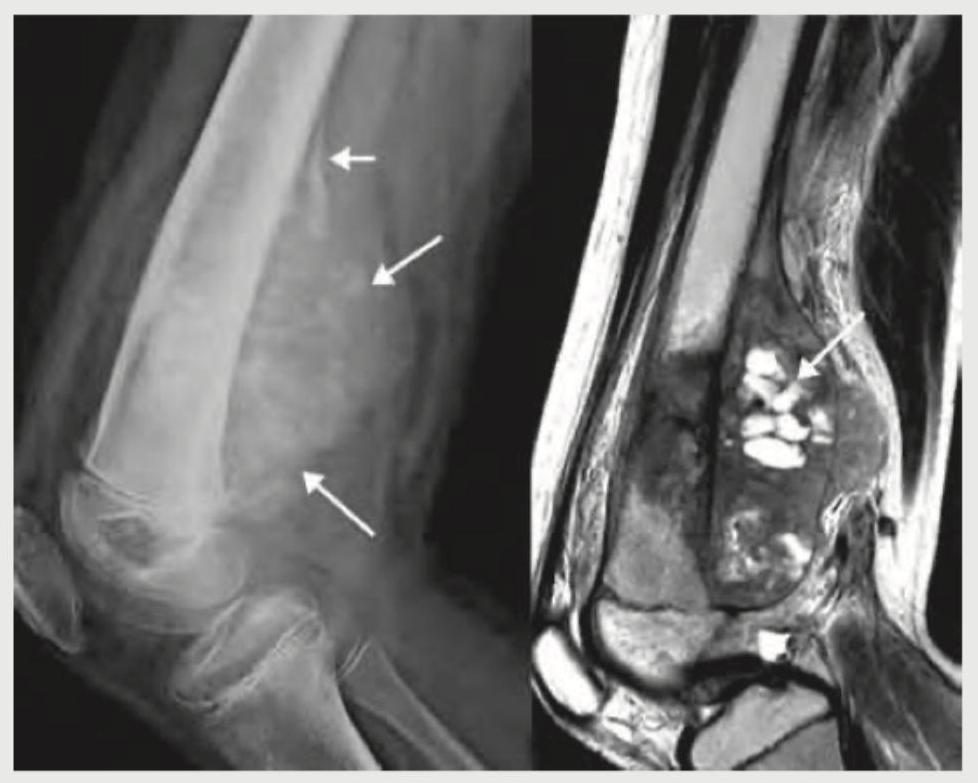

The X-ray and MRI findings given below point to the diagnosis of: (Recent NEET Pattern 2016-17)

Explanation: ***Pigmented villonodular synovitis*** - The MRI image shows characteristic **low signal intensity foci** on T1 and T2 weighted images due to hemosiderin deposition, along with a nodular synovial mass, which are hallmarks of **pigmented villonodular synovitis (PVNS)**. - The presence of multiple nodular lesions within the joint capsule (indicated by arrows on MRI) and the soft tissue swelling visible on X-ray, without significant bone destruction typically seen in aggressive tumors, is consistent with PVNS. *Osteoid osteoma* - An osteoid osteoma typically appears as a **small lucent nidus** (<1.5 cm) with a sclerotic rim in the bone, often associated with a painful presentation relieved by NSAIDs. - The imaging findings here, particularly the large soft tissue mass and hemosiderin deposits on MRI, are not characteristic of an osteoid osteoma. *Osteoclastoma* - Osteoclastomas, also known as **giant cell tumors of bone**, are aggressive but benign tumors that appear as expansile **lytic lesions** originating in the epiphysis/metaphysis of long bones. - While they can be destructive, they typically don't present with the diffuse, hemosiderin-laden synovial proliferation seen in these images. *Osteosarcoma* - Osteosarcoma is a highly malignant bone tumor characterized by the production of **osteoid matrix** and often presents with features like cortical destruction, a soft tissue mass, and a sunburst or Codman's triangle appearance on X-ray. - The imaging features shown, particularly the T1/T2 hypointense foci on MRI due to hemosiderin, are not typical for osteosarcoma, which would instead show more features of bone destruction and aggressive periosteal reaction.